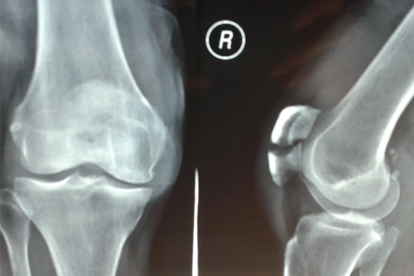

髌骨骨折后应尽早开始康复训练,在医生指导下进行直腿抬高、踝泵运动预防肌肉萎缩。保证每日摄入足量优质蛋白如鱼肉蛋奶,补充维生素D促进钙吸收。定期复查X线观察骨折愈合情况,逐步增加膝关节活动度训练强度,避免剧烈运动导致二次损伤。出现明显肌力下降或肌肉挛缩时需及时就医进行专业评估。